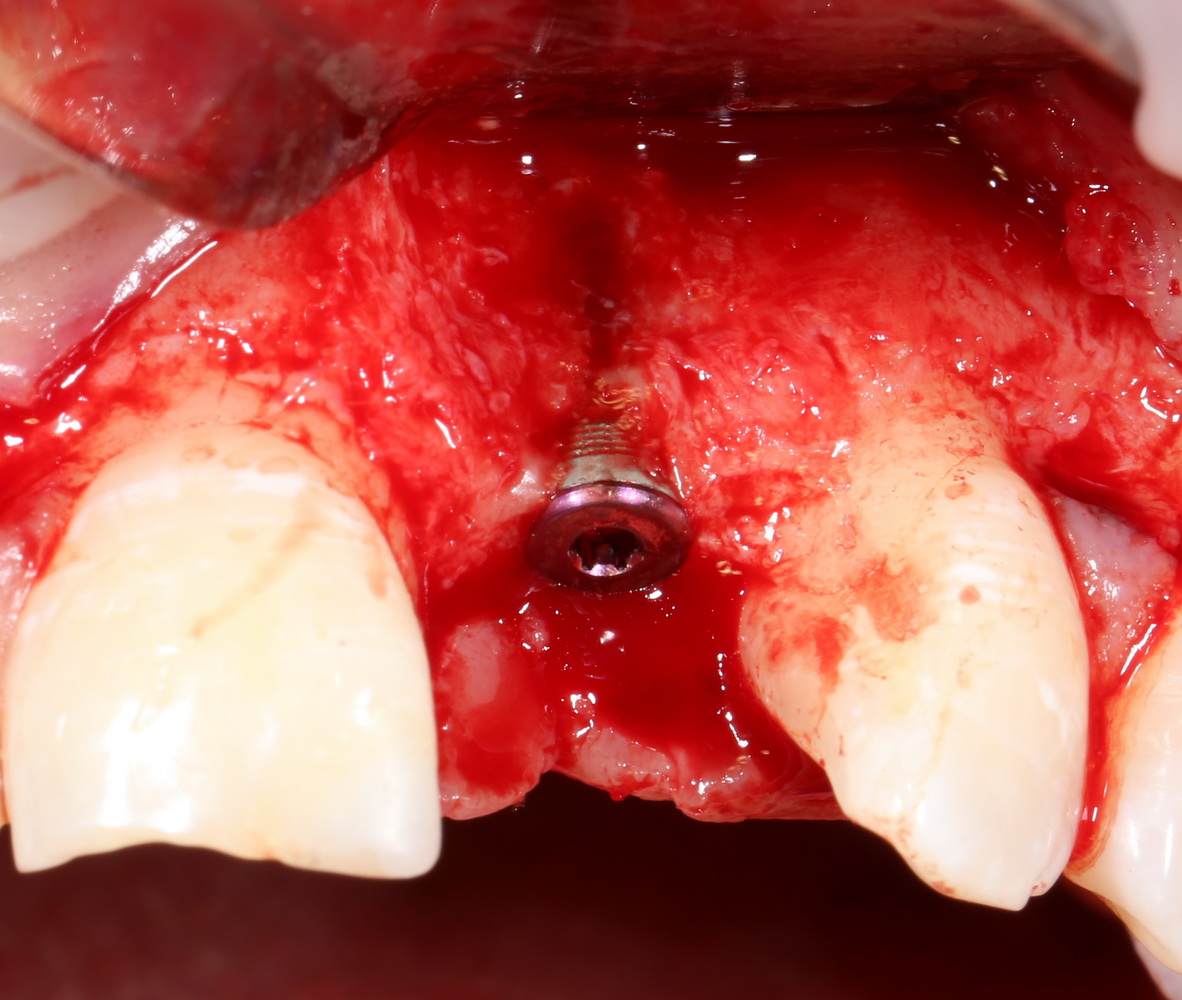

Например, в следующей ситуации:

Оставить так, как есть — это значит, сильно рисковать имплантом и объемом альвеолярного гребня — фактически, большая часть импланта пятого зуба «висит в воздухе». Поэтому получившуюся костную полость мы заполняем аутокостной стружкой в смеси с Bioss и закрываем коллагеновой мембраной BioGide: